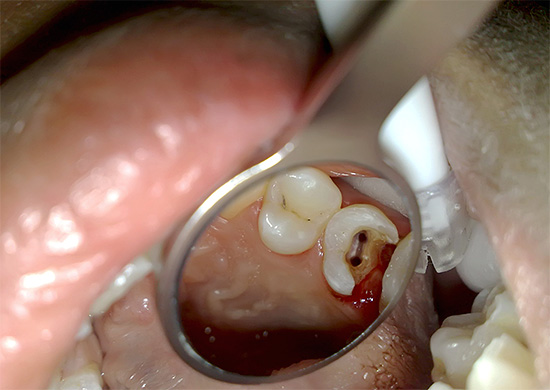

Come risultato del trattamento di scarsa qualità della pulpite a tre canali in un'organizzazione di bilancio, i seguenti problemi possono sorgere in breve tempo:

- dolore ai denti sullo sfondo di canali scarsamente lavati, sigillati in modo incompleto o a causa della rimozione di materiale di riempimento esterno alla radice (danneggerà il morso);

- gonfiore delle gengive e delle guance con canali mancati (con infezione) o un frammento di uno strumento dentale lasciato nel canale, il che non è raro (vedi foto sotto);